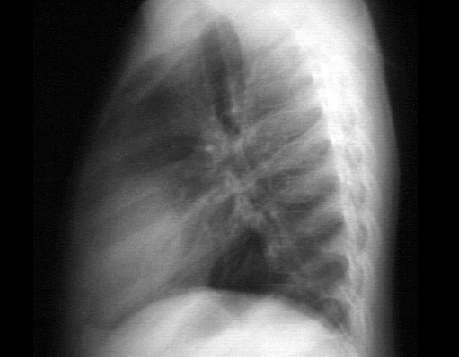

This lateral view demonstrates the pericardial cyst as well. It appears as a double density over the heart shadow.